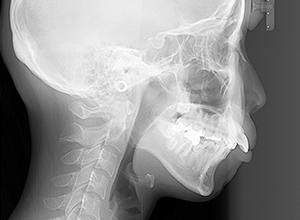

初診時

FP・IOP

X-Ray

X-Ray所見

セファロ所見 下顎骨体部は小さくないものの下顎枝は短く、下顎頭は後方に位置付き中顔面高は高いため、下顎はクロックワイズローテーションしており、前後的にはII級の骨格形態を示していた。

パノラマ所見 上下顎両側第三大臼歯は埋伏していた。下顎右側大臼歯から犬歯まで近心傾斜し、左側においては左下5を境に大臼歯は近心傾斜、近心の歯は遠心方向へ傾斜が認められた。